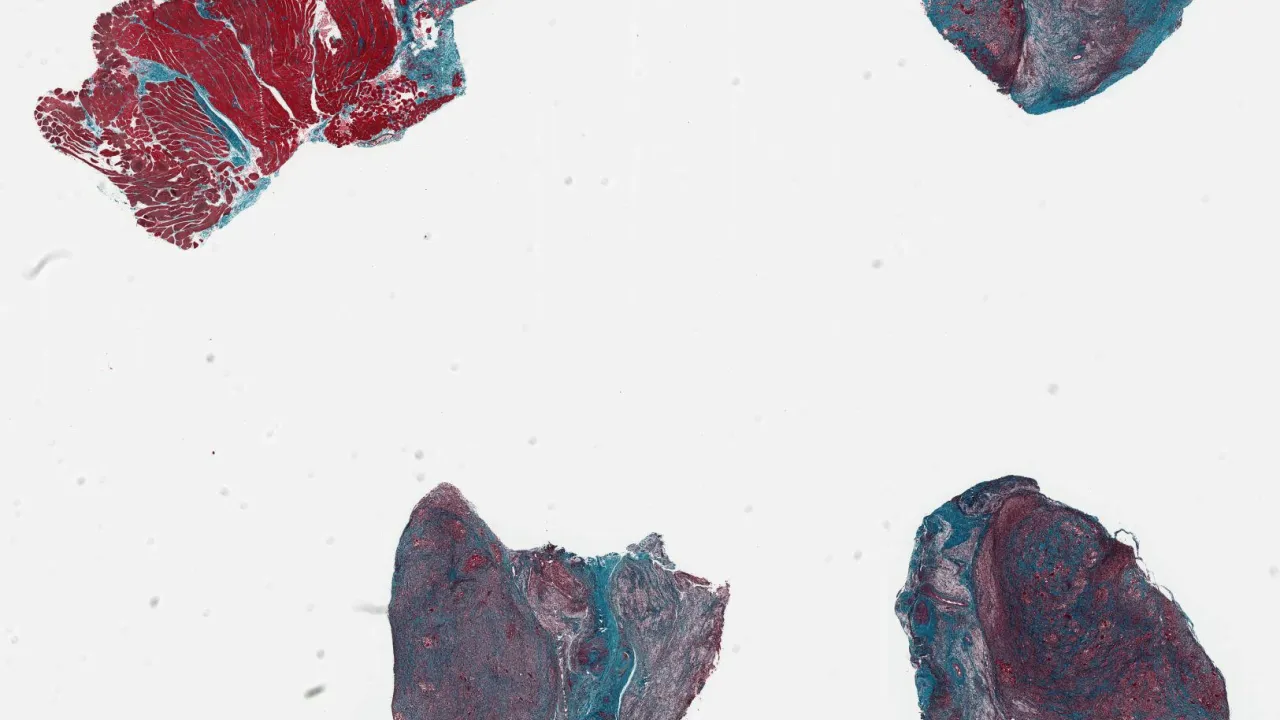

Liver, Inactive cirrhosis, Trichrome stain